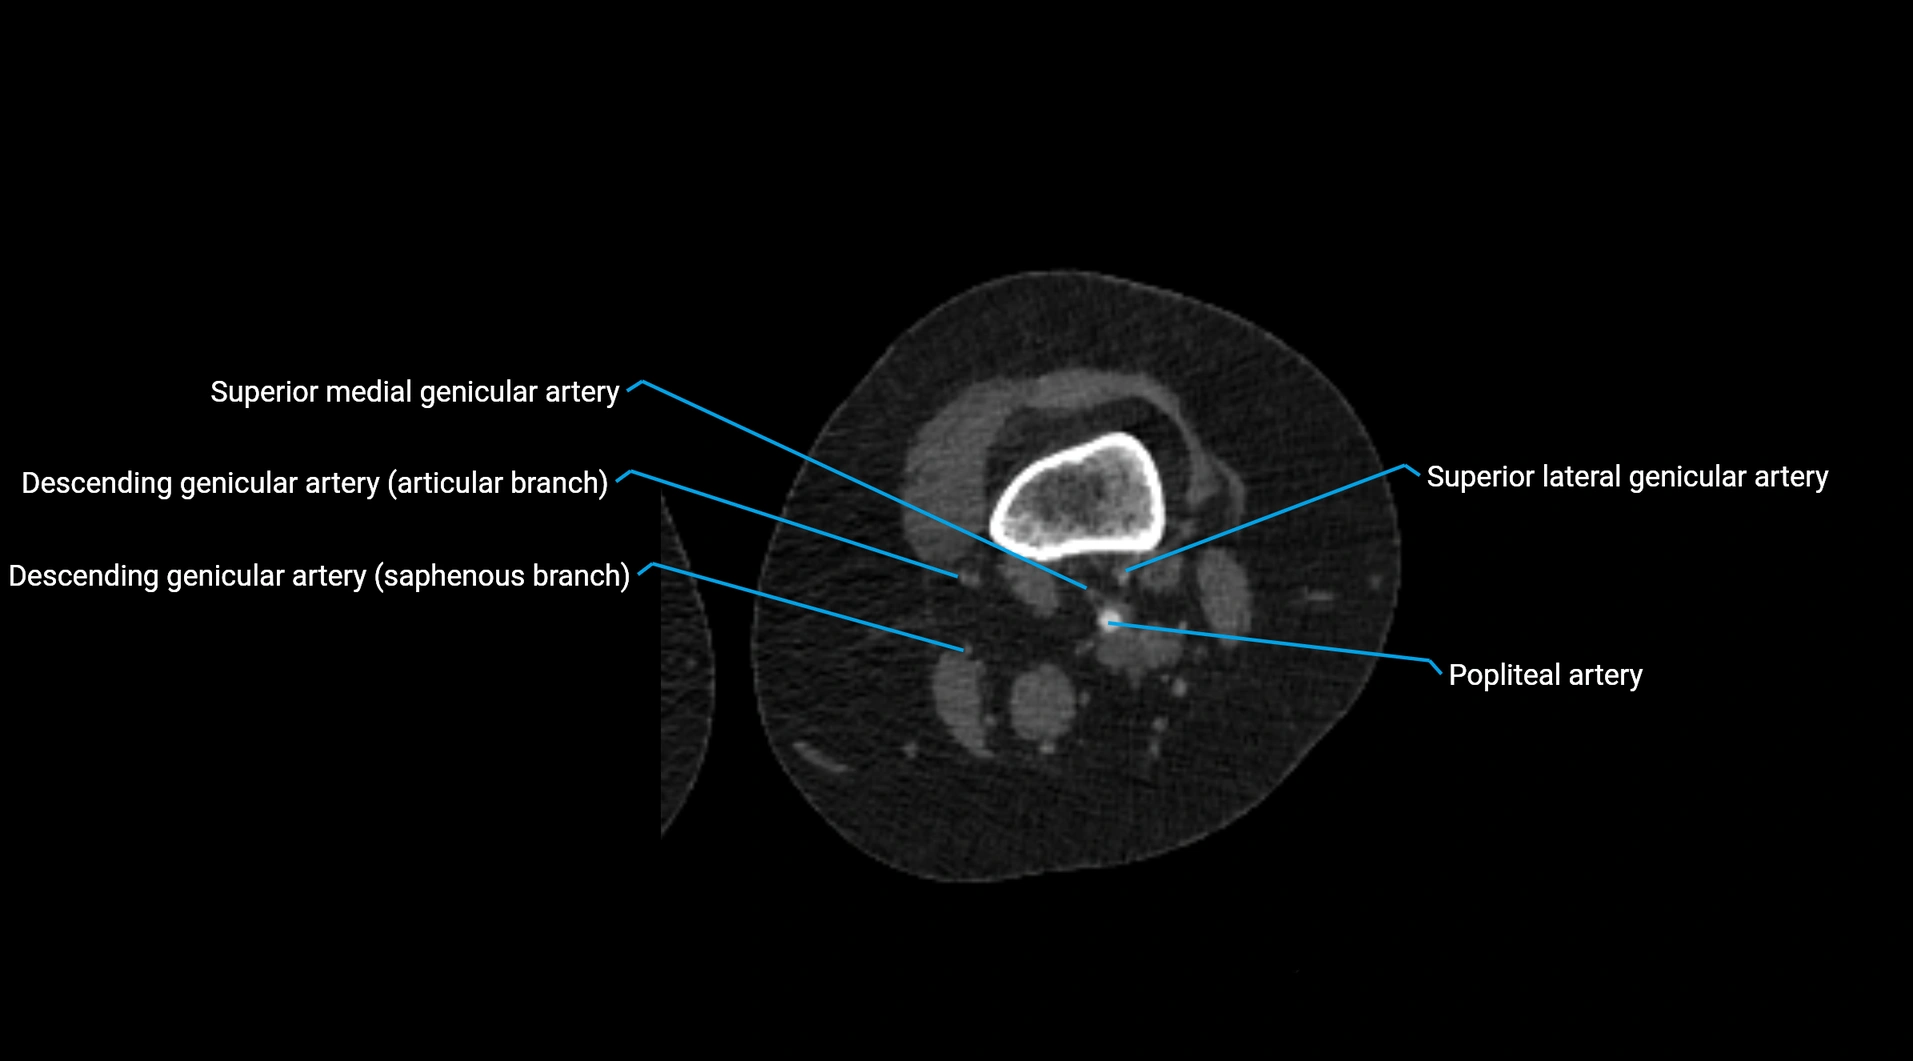

Contrast-enhanced CT (CTA):

• Gold standard for abdominal aortic imaging

• Provides excellent detail of lumen, wall, aneurysm, thrombus, and branch vessels

• Multiplanar and 3D reconstructions help in aneurysm measurement, stent graft planning, and dissection evaluation